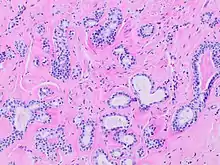

Human submandibular gland. At the right is a group of mucous acini, at the left a group of serous acini. | |